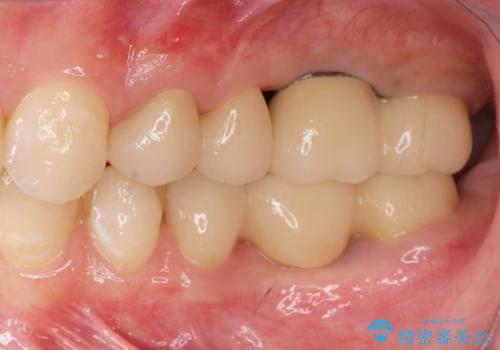

虫歯・破折の放置により重度に吸収した歯槽骨 骨造成後のインプラント治療

X線検査の結果、左上6には歯根破折、左上7には銀歯の下に大きな虫歯の再発が認められ共に抜歯をせずには症状の改善が見込めない状況です。

奥歯を2本失ったのち、しっかりと噛める環境へと整備するため、しっかりと骨の造成を行い清掃性を高めたインプラント治療を行っていくこととしました。

インプラントの仕上がりを見越して、ただ埋入するだけではなく長期的な予後を見込むには清掃のしやすい環境を整備することが大切です。

今回は大きく吸収してしまった歯槽骨をしっかりと造成することで、歯間ブラシを行いやすいインプラント周囲環境を整備することができました。